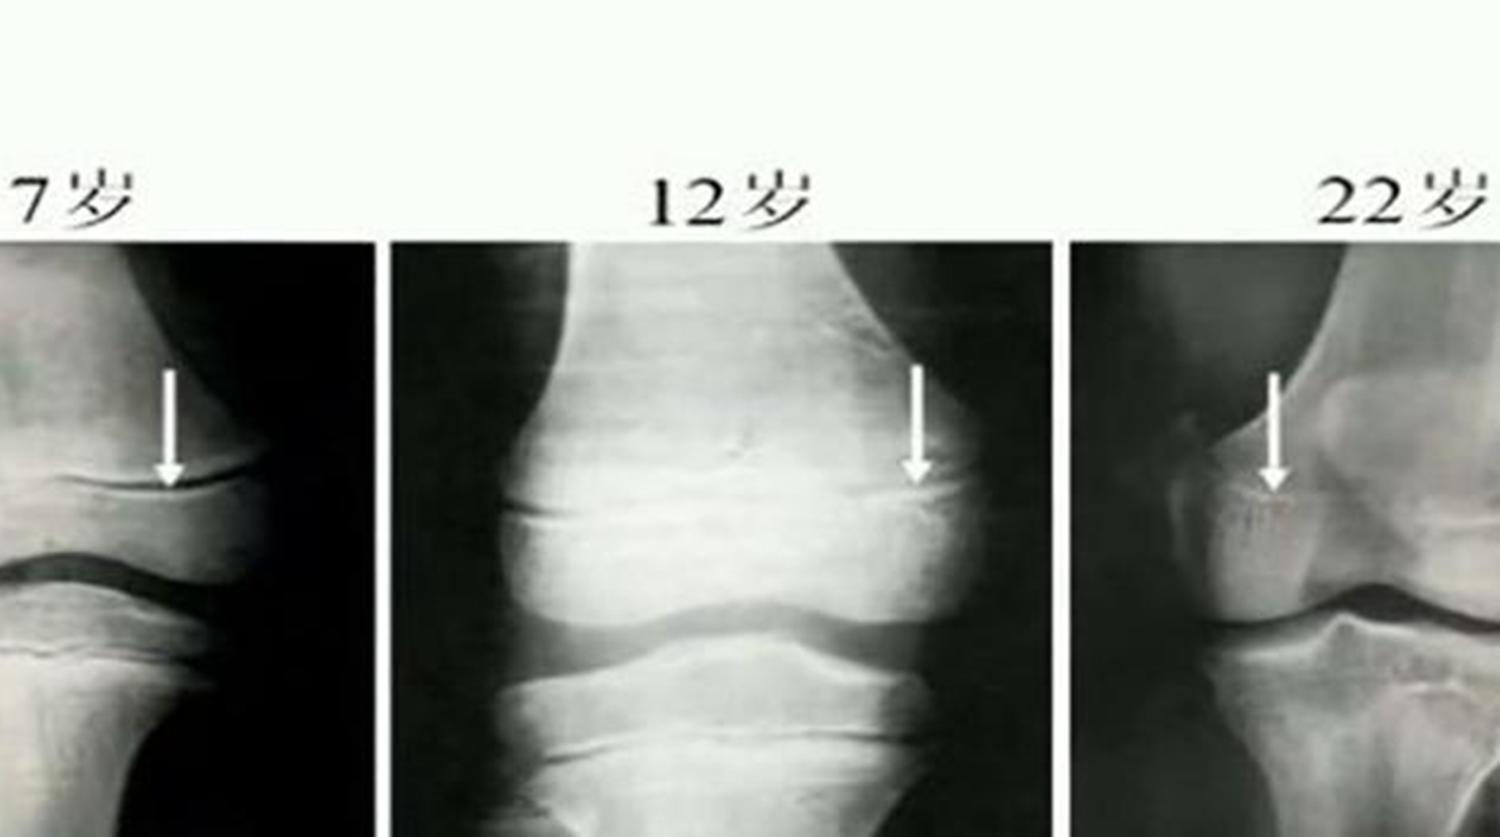

孩子骨骼成长发育,最重要的一个要害点是“骨骺线”,也就是说想让孩子长高,最要害的就是抓住孩子骨骺线闭合时间,在此之前努力。

一般情况下,男孩子的骨骺线在18岁左右的时候会完全闭合,女孩子的则会在16左右就闭合,但每个人的身体情况不一样,骨骺线闭合的具体时间也有着差异,而且也会延长。